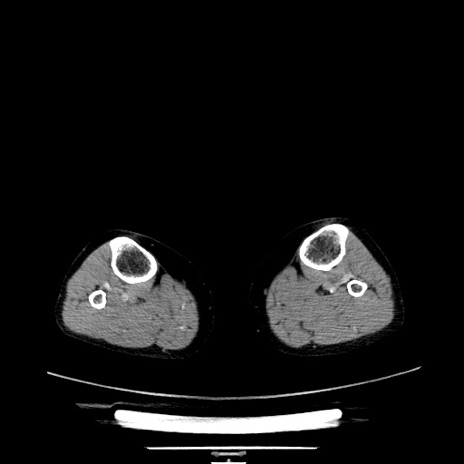

【症例】70歳代女性

【主訴】お腹が張る

【現病歴】1週間くらい前から腹部膨満の自覚あり。昨日夜から増悪したため、本日救急外来受診。

【身体所見】意識清明、BT 36.5℃、BP 165/106mmHg、HR 80bpm、SpO2 98%、腹部:膨満、軟、自発痛・圧痛なし、触診にて不快感あり、腸蠕動音:減弱

【データ】WBC 12600、CRP 1.04